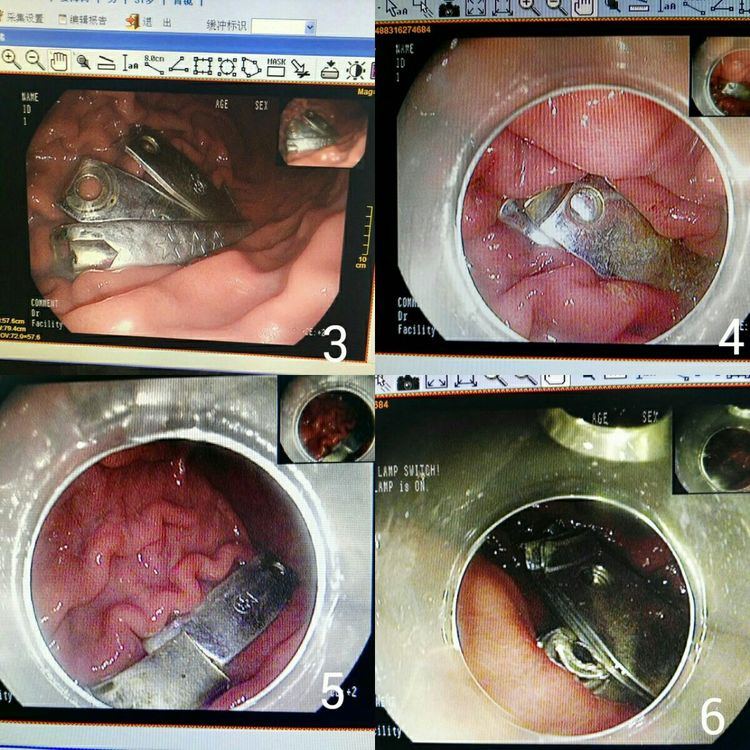

图3、4、5、6显示异物在胃体皱褶中,4块指甲刀残片,可以看到刀刃和锋利的断端。